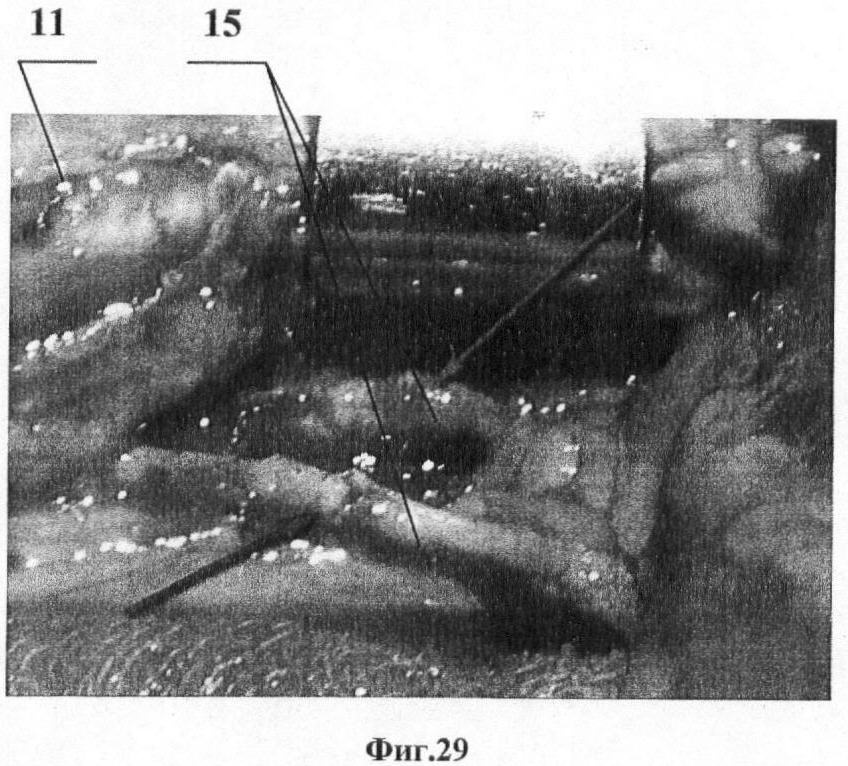

Поскольку иллюстративные материалы в отличие от описания и формулы изобретения не имеют правового значения, носят факультативный характер и представляются лишь для более ясного и четкого понимания обязательных элементов заявки (Коментарий к Гражданскому Кодексу Российской Федерации, часть четвертая, ст.1375, п.8, изд. Проспект, 2007), ход и схема выполнения оперативного вмешательства по заявленному способу представлены ниже в виде рисунков и фотографий. На рисунках показано: на фиг.1 показан доступ для эндоскопического забора лоскута передней зубчатой мышцы; на фиг.2 – рамка кольцевой формы; на фиг.3 – рамка криволинейной формы; на фиг.4. – внешний вид тракционного механизма; на фиг.5 – подвеска груза, кожа приподнята; на фиг.6 – обнажение переднего края широчайшей мышцы спины и наружной поверхности передней зубчатой мышцы; на фиг.7 – выделение первого сосуда; на фиг.8 – выделенные и идентифицированные сосуды взяты на держалки; на фиг.9 – передний край широчайшей мышцы спины приподнят, сосуды идентифицированы, проксимальная диссекция сосудистой ножки, дополнительный проксимальный портал; на фиг.10 – начало диссекции в поверхностной фасциальной расщелине; на фиг.11 – окончание диссекции в поверхностной фасциальной расщелине; на фиг.12 – выкраивание мышечной части лоскута, дополнительный дистальный портал; на фиг.13 – начало диссекции в глубокой фасциальной расщелине; на фиг.14 – окончание диссекции в глубокой фасциальной расщелине; на фиг.15 – лоскут извлечен из нативного места, гемостаз донорского ложа; на фиг.16 – лоскут готов к транспонированию, сосудистую ножку сохраняют до окончательной подготовки реципиентных сосудов; на фиг.17 – основной и дополнительные порталы ушиты, аспирационное дренирование; на фиг.18 – транспонирование и подгонка лоскута; на фиг.19 – реконструируирование мягкотканого дефекта, замещение дефекта лоскутом. На фотографиях показано: фиг.20 – раненый Г., рубцовый дефект левой пяточной области; фиг.21 – раненый Г., рентгенограммы стопы, остеомиелит пяточной кости, снижение угла Белера; фиг.22 – раненый Г., предоперационная разметка реципиентной области; фиг.23 – раненый Г., предоперационная разметка донорской области; фиг.24 – раненый Г., положение больного на операционном столе; фиг.25 – раненый Г., выделение первого сосуда через основной портал; фиг.26 – раненый Г., эндоскопическая диссекция сосудистой ножки; фиг.27 – раненый Г., выкраивание мышечной части лоскута; фиг.28 – раненый Г., лоскут передней зубчатой мышцы извлечен из нативного места; фиг.29 – раненый Г., микрососудистый шов по типу «конец-в-конец» артерии (красная стрелка) и вены (синяя стрелка); фиг.30 – раненый Г., лоскут укрыт расщепленным кожным трансплантатом; фиг.31 – раненый Г., артериограмма области реконструкции; фиг.32 – раненый Г., внешний вид области реконструкции через 1 месяц после операции; фиг.33 – раненый Г., внешний вид и функция донорской области через 6 месяцев после операции, рука поднята; фиг.34 – раненый Г., внешний вид и функция донорской области через 6 месяцев после операции, рука опущена.

Пациент Г., получил осколочное ранение левой пяточной области во время вооруженного конфликта на Северном Кавказе в 1999 году. Раневой процесс осложнился хроническим огнестрельным остеомиелитом пяточной кости, сопряженным с мягкотканым дефектом нагружаемой поверхности пяточной области. В лечебных учреждениях выполнялась дерматотензия и пластика местными тканями. Несмотря на купированный остеомиелитический процесс и эпителизацию раны возникший рубцовый дефект размерами 7×5 см нагружаемой зоны служил причиной значительных функциональных нарушений конечности (фиг.20, фиг.21). После предоперационного планирования (фиг.22-23 в положении больного на боку (фиг.24) были иссечены рубцы и подготовлены к анастомозированию сосуды в реципиентном ложе. Далее выполнен эндоскопический забор свободного лоскута передней зубчатой мышцы (фиг.25 – фиг.38). Лоскут транспонирован в реципиентное ложе, выполнено микрососудистое анастомозирование (фиг.29), а сам лоскут покрыт расщепленным аутодермотрансплантатом 18 (фиг.30). Реконструкция лоскута была состоятельной (фиг.31, фиг.32), послеоперационный период протекал без осложнений, а морбидность донорского места 19 (фиг.33, фиг.34) оценена как низкая, а перфузия лоскута состоятельна, дефект реконструирован с удовлетворительным результатом.